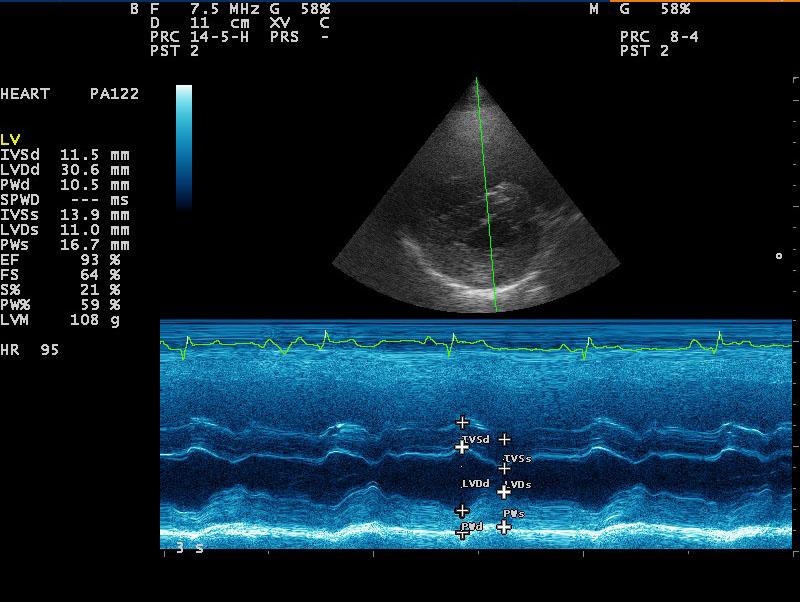

A 10-year-old SF Labrador was presented for evaluation of ascites, which was quantified as a modified transudate. Additional history on this dog was that 11 months prior an ovariohysterectomy and resection of mammary gland tumors had been done. The tumors were benign on histopathology. On abdominal ultrasound, the ascites, hepatic congestion, and a dilated CVC were present.